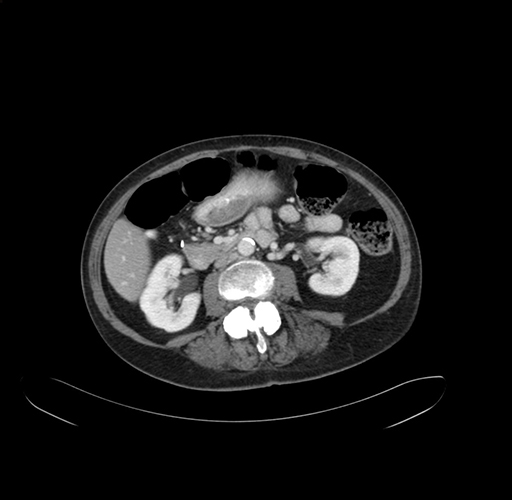

Pre-Chemo: Axial Venous

Axial Venous